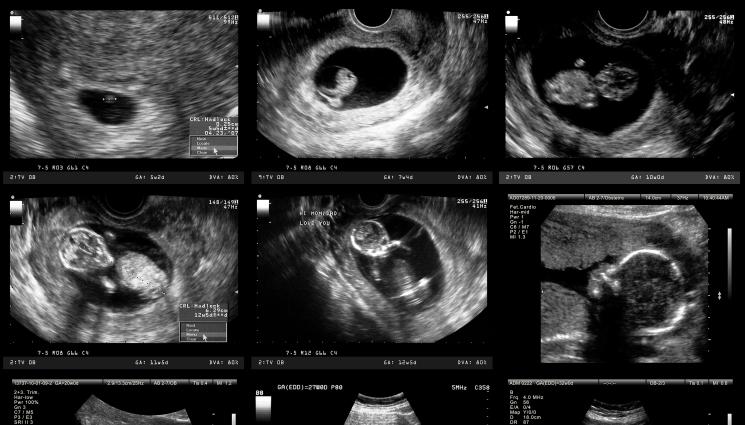

Doctors found that Sanju Bhagat suffered from one of the world’s most bizarre medical conditions- fetus in fetu. pic.twitter.com/PaPLn9Mheu

Оказало се, че мъжът през цялото време е развивал аномалия, която се нарича „Ембрион в ембриона“. Неговият брат близнак живеел в корема му като паразит.